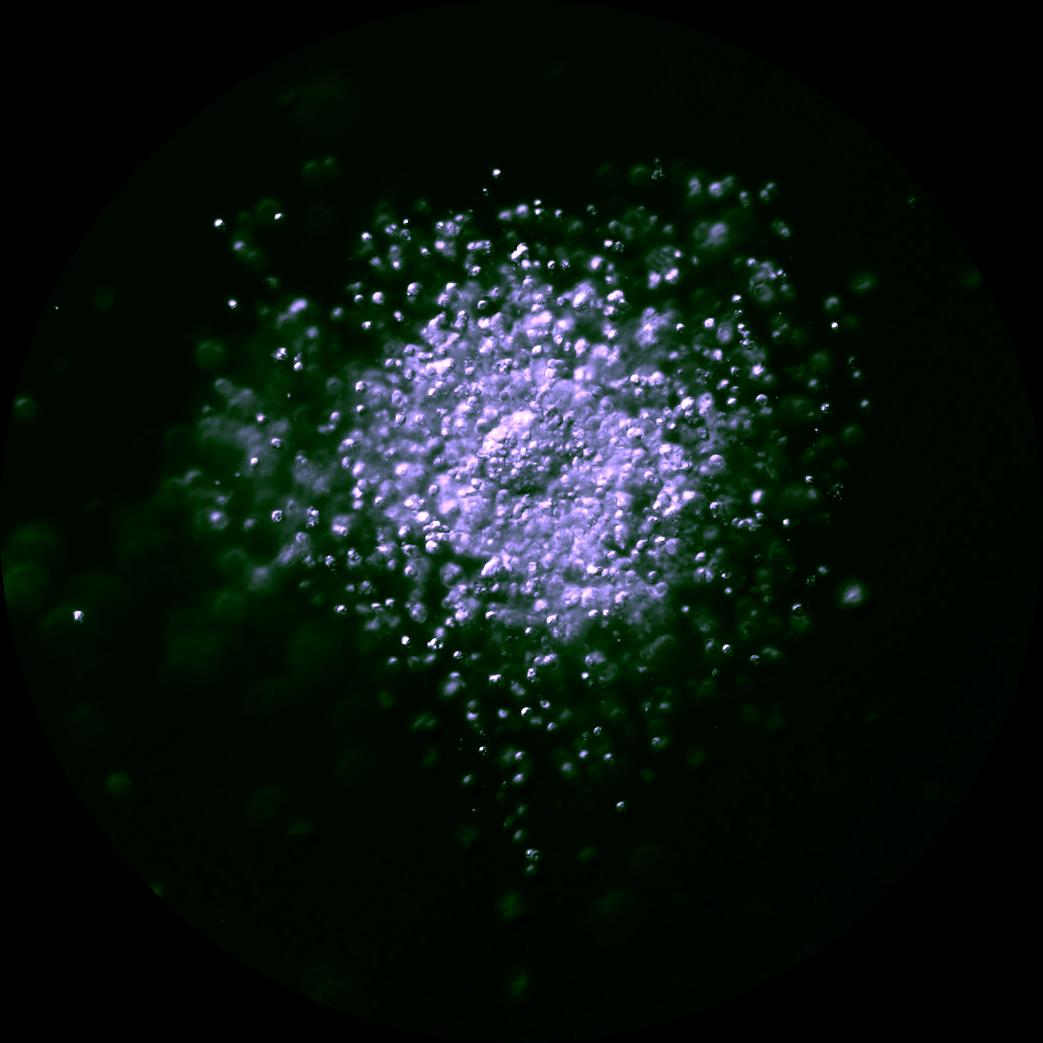

Much of the research at the CHR has focused on why some oocytes are fully mature after trigger and why others fail to either initiate or complete the maturation process. Dr. Albertini has spent much of his career trying to understand the fascinating dialogue that exists between the oocyte and cumulus cells and here in this image is an example of one of his CHR research projects. Looking down on the surface of a human oocyte, many cumulus cells can be seen and using special staining techniques. Cumulus cells “reach out and touch” the oocyte using fine extensions referred to as Transzonal Processes or TZPs for short. TZPs serve as conduits for supplying the oocyte with both nutritional and informational molecules that tell the oocyte to mature and prepare for fertilization, key elements in the underlying biology that will dictate which oocytes go on to develop as an embryo-or not.